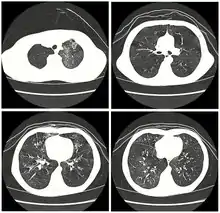

| High resolution CT scan showing bronchiolitis obliterans with mosaic attentuation, bronchiectasis, air trapping and bronchial thickening[3] | |

Early in the disease chest radiography is typically normal but may show hyperinflation.[6] As the disease progresses a reticular pattern with thickening of airway walls may be present.[4][6] HRCT can also show air trapping when the person being scanned breathes out completely; it can also show thickening in the airway and haziness in the lungs.[11] A common finding on HRCT is patchy areas of decreased lung density, signifying reduced vascular caliber and air trapping.[6] This pattern is often described as a "mosaic pattern", and may indicate obliterative bronchiolitis.[6]